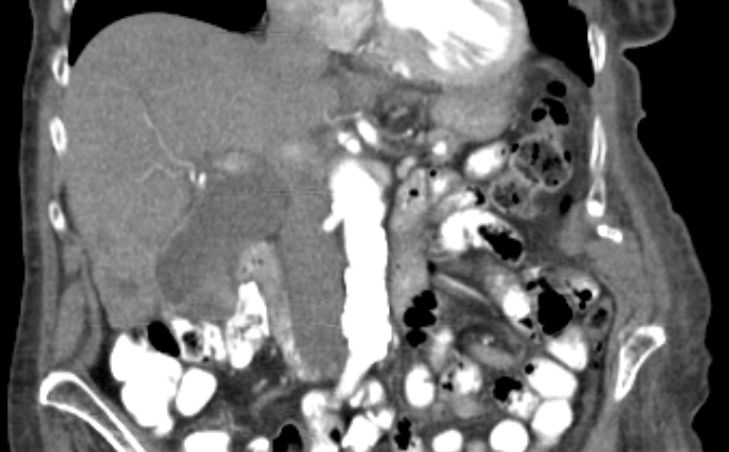

86-jähriger Mann, bei dem vor 9 Monaten eine Cholezystektomie wegen gedeckt perforierter Cholezystitis vorgenommen wurde. Jetzt Verdacht auf Leberabszess. Die laparoskopische Biopsie ergab ein Adenokarzinom. Die Nachbefundung der Gallenblase erbrachte immunhistochemisch den Nachweis eines Gallenblasenkarzinoms. | ||